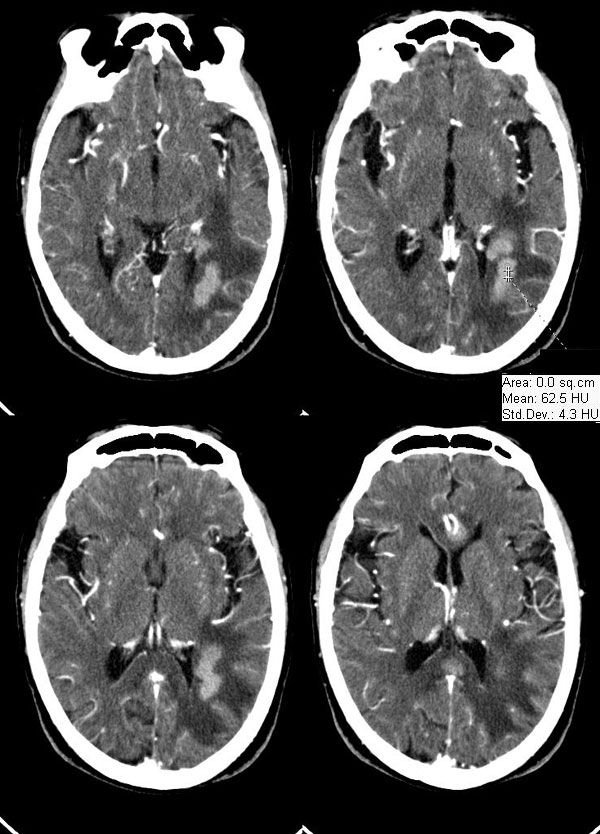

病灶平扫ct值约38hu,强化后明显强化,ct值约63hu,有一层ct值约72hu,病史:病人,男75,血压120/75,不高,头晕12天,平时体健,当时曾作胸x线片,正常。腹部ct,肝多发囊肿。经治疗(林格液+甘露醇)未用营养液及化疗药,当时诊断转移瘤。12天复查片如下

胼胝体见多个明显强化结节影,周围水肿轻,左颞枕交界区见呈腊肠状强化灶,周围水肿明显,多发病灶均有占位效应,首先考虑淋巴瘤,水肿轻,位置深,强化明显,其次转移瘤?

胼胝体见多个明显强化结节影,周围水肿轻,左颞枕交界区见呈腊肠状强化灶,周围水肿明显,多发病灶均有占位效应,首先考虑淋巴瘤(水肿轻,位置深,强化明显)其次转移瘤? 建议追问病史?

胼胝体见多个明显强化结节影,周围见低密度水肿灶;左颞枕交界区见呈腊肠状强化灶,增强后强化明显,周围指状水肿。多发病灶均有占位效应,水肿轻,位置深,强化明显。

胼胝体膝部及压部各见一明显强化结节影,周围水肿轻,左颞枕交界区见呈腊肠状强化灶,周围水肿明显,多发病灶均有占位效应。

左颞枕交界区及胼胝体多发明显而均匀强化的实性肿块。

沟脑回加深增宽证像,特别是双侧外侧裂池增宽明显,因是老年患者,病灶位置深且都在侧脑室旁,呈腊肠状,边界清,有轻占位和水肿。

首先考虑淋巴瘤;转移瘤也可考虑,但病灶虽为多发,但位置深在,与其好发于大脑皮质及皮质下区的特点不符。